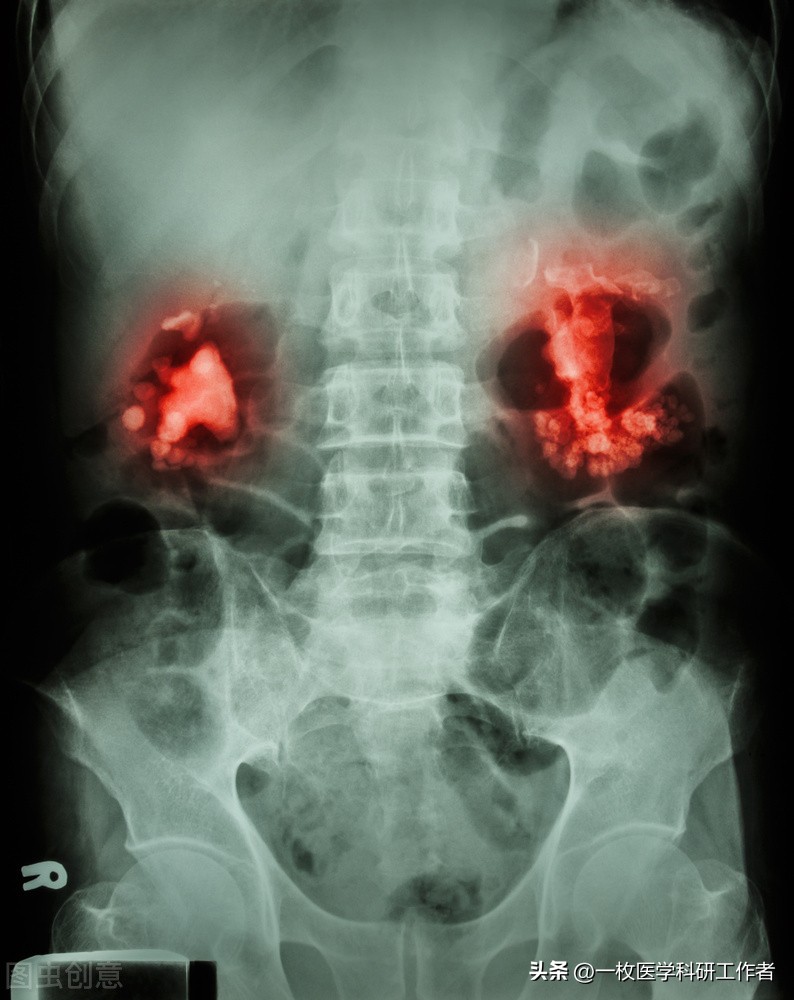

肾结石

双侧肾结石